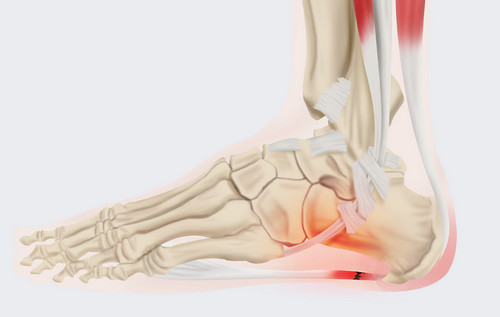

족저 근막염이란?

족저근막염이란 발바닥 뒤꿈치에 염증이 생기면서 나타나는 발바닥 통증을 일컫습니다. 이는 남성보다 여성이 2배 정도 많이 발병된다고 하는데, 그 원인은 과도한 발의 스트레스나 운동으로 인해 발병된다고 합니다. 이 밖에 몸무게의 급격한 증가나 평발도 발병 확률을 높이는 원인이 됩니다.

족저 근막염의 가장 흔한 증상으로는 아침에 통증이 매우 심하다는 점입니다. 그 이유는 밤사이에 족저근막이 수축되었다가 잠에서 깨서 일어나며 지면을 내딛는 순간 스트레칭 되면서 통증이 발생되기 때문입니다. 보통 원인은 종아리의 과단축으로 인하여 발바닥 근막이 당겨지면서 발병하는 경우가 대부분입니다. 때문에 족저 근막염을 예방하려면 평소 종아리와 발바닥을 같이 관리해 주어야 합니다. 만약 족저 근막염에 걸린 경우에는 생활 개선과 함께 필요에 따라 약물이나 의료적 치료가 병행되어야 합니다.